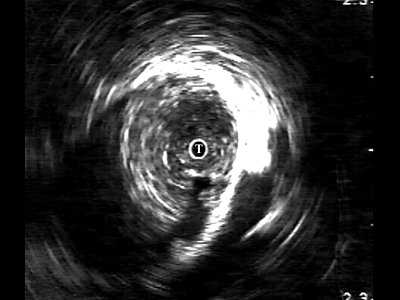

Четко визуализируются патологические образования в паренхиме (рис. 4). В зоне стриктуры мочеиспускательного канала определяется различной протяженности и глубины фиброзная ткань в виде гиперэхогенных участков.

Рис. 4. Эхограмма простатического отдела уретры.